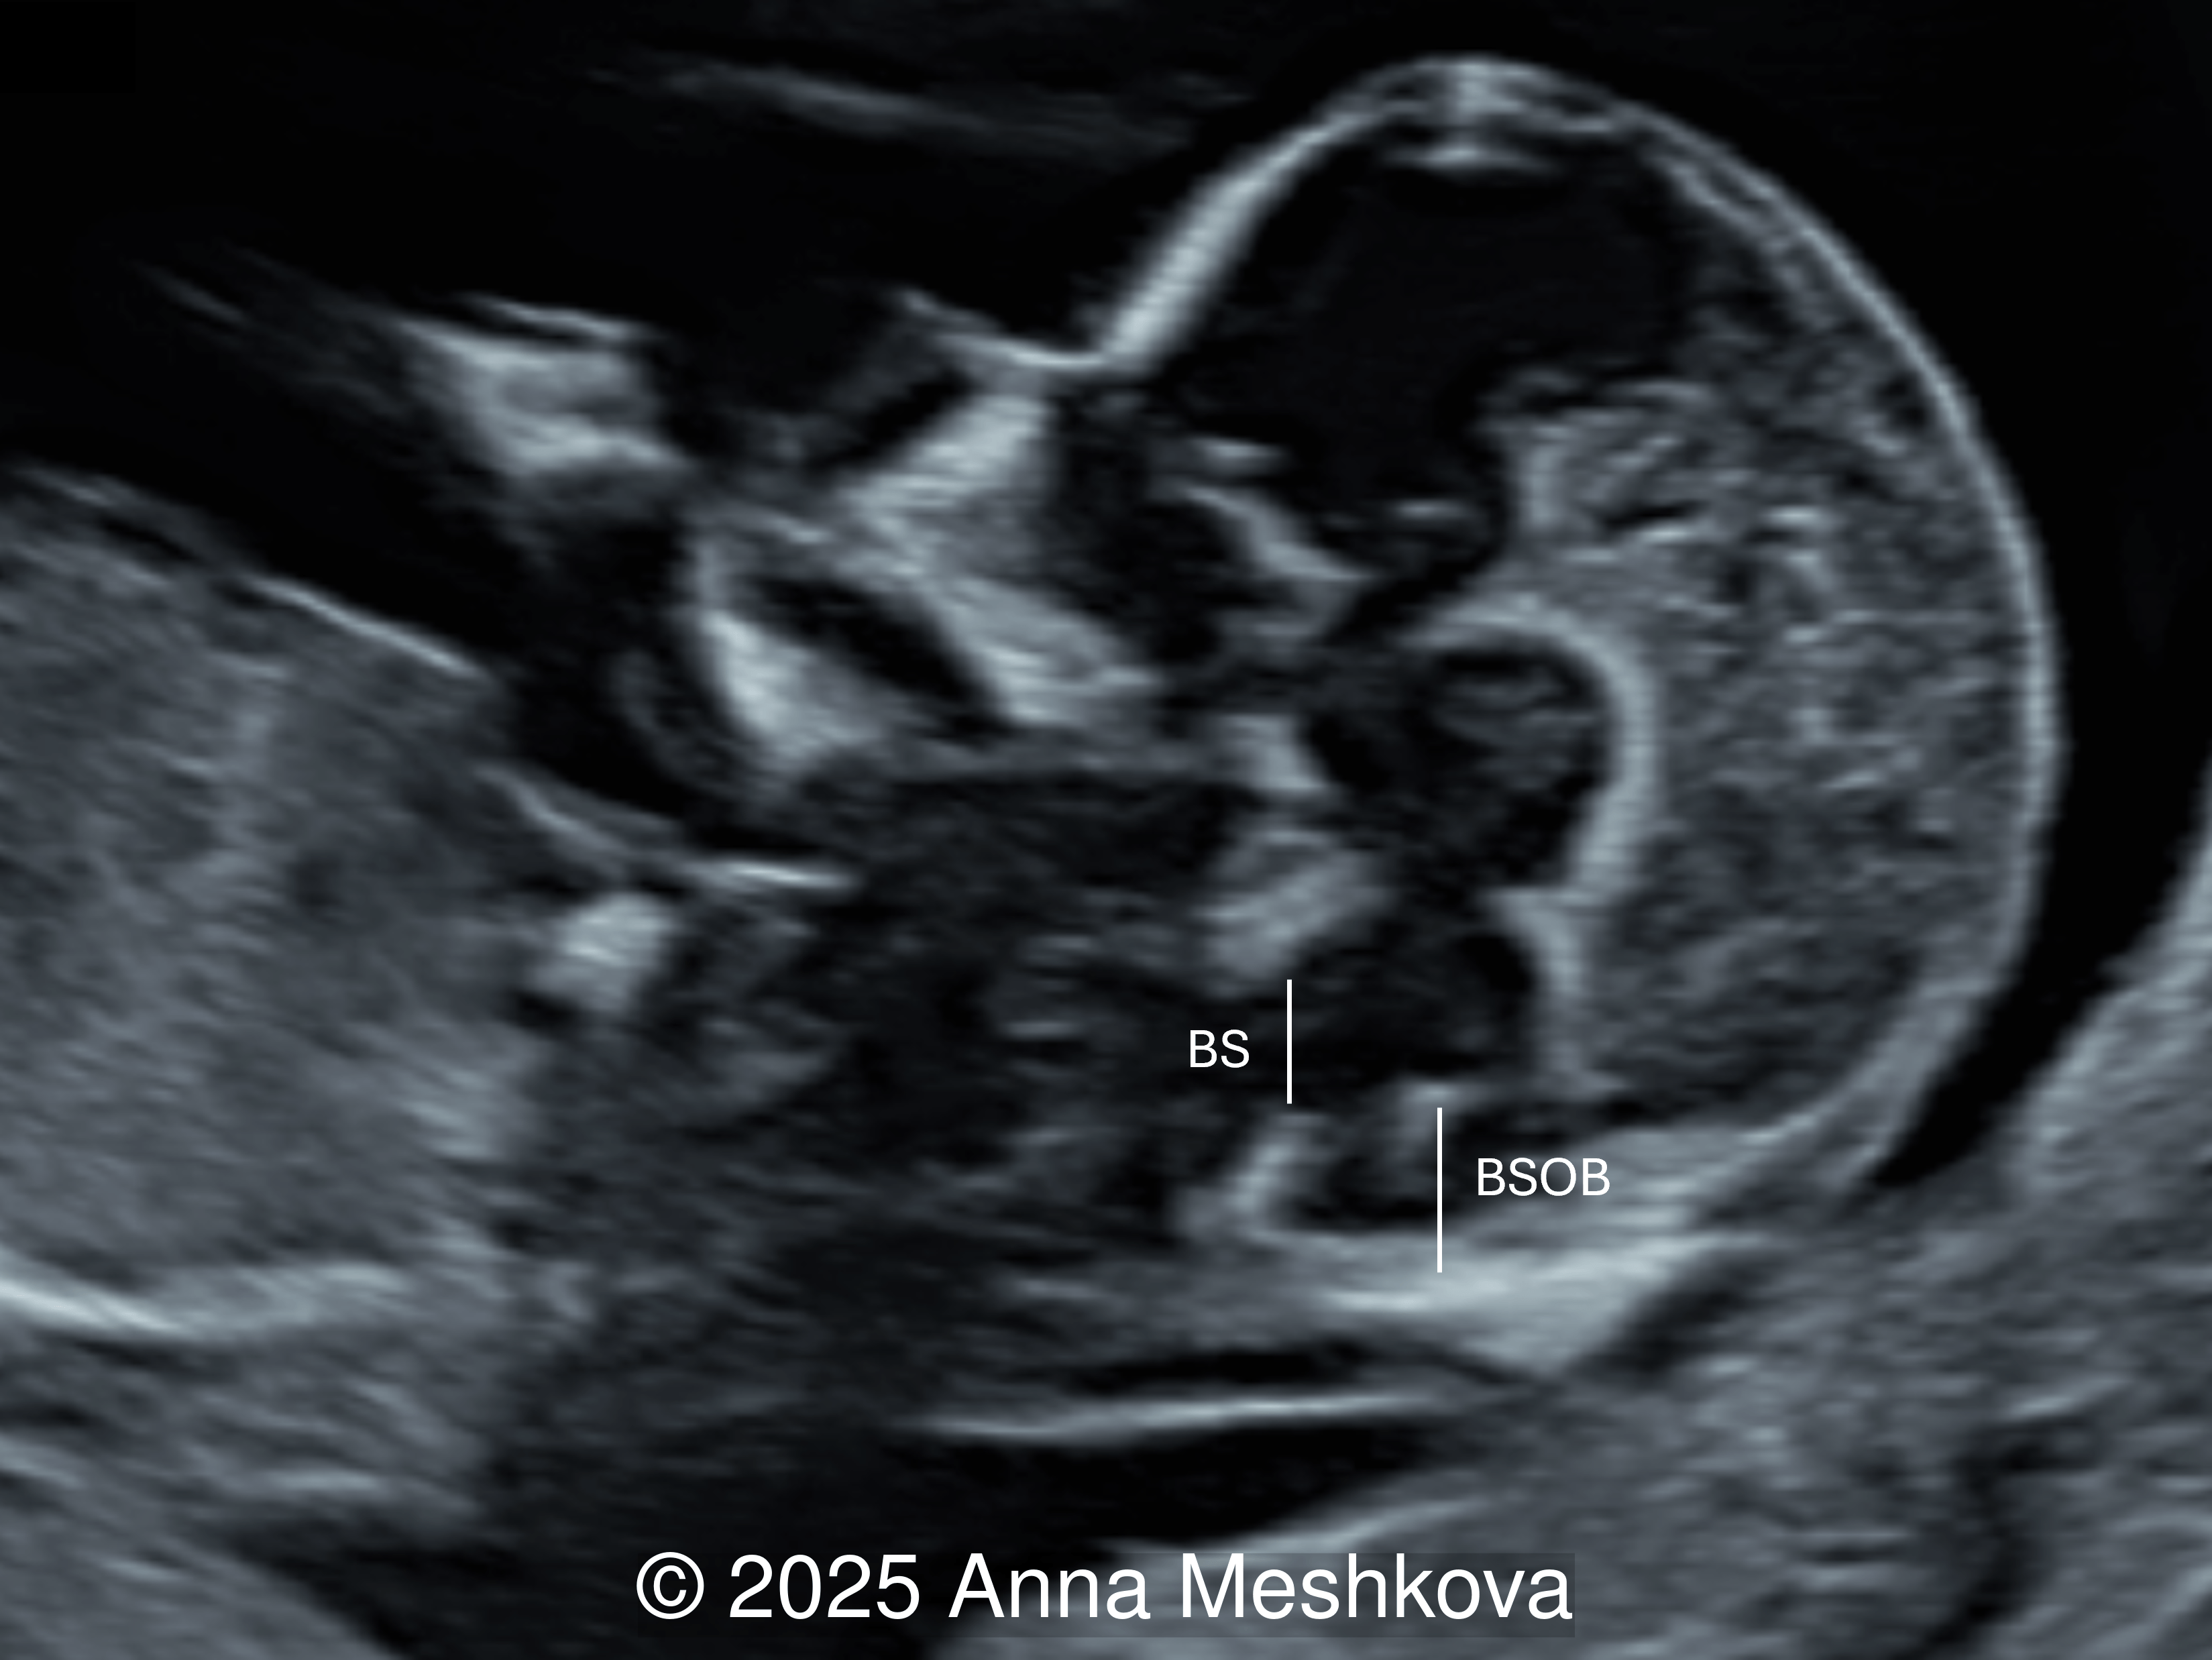

2.  Brainstem and Brainstem-Occipital Bone (BSOB) Distance measurements can suggest the diagnosis of open spina bifida. An increased brainstem diameter with reduced BSOB distance results in an elevated BS:BSOB ratio, which is a reliable indicator of open spina bifida.  In fetuses with open spina bifida compared to normal fetuses, the brain stem diameter (BS) is higher, the BSOB diameter is lower resulting in an increased BS:BSOB ratio [2].

In a normal fetus, the brainstem (BS) is relatively narrow and shorter in length than the brainstem–occipital bone (BSOB) distance.

In a fetus with spina bifida, there is brainstem thickening and an increased BS:BSOB distance ratio